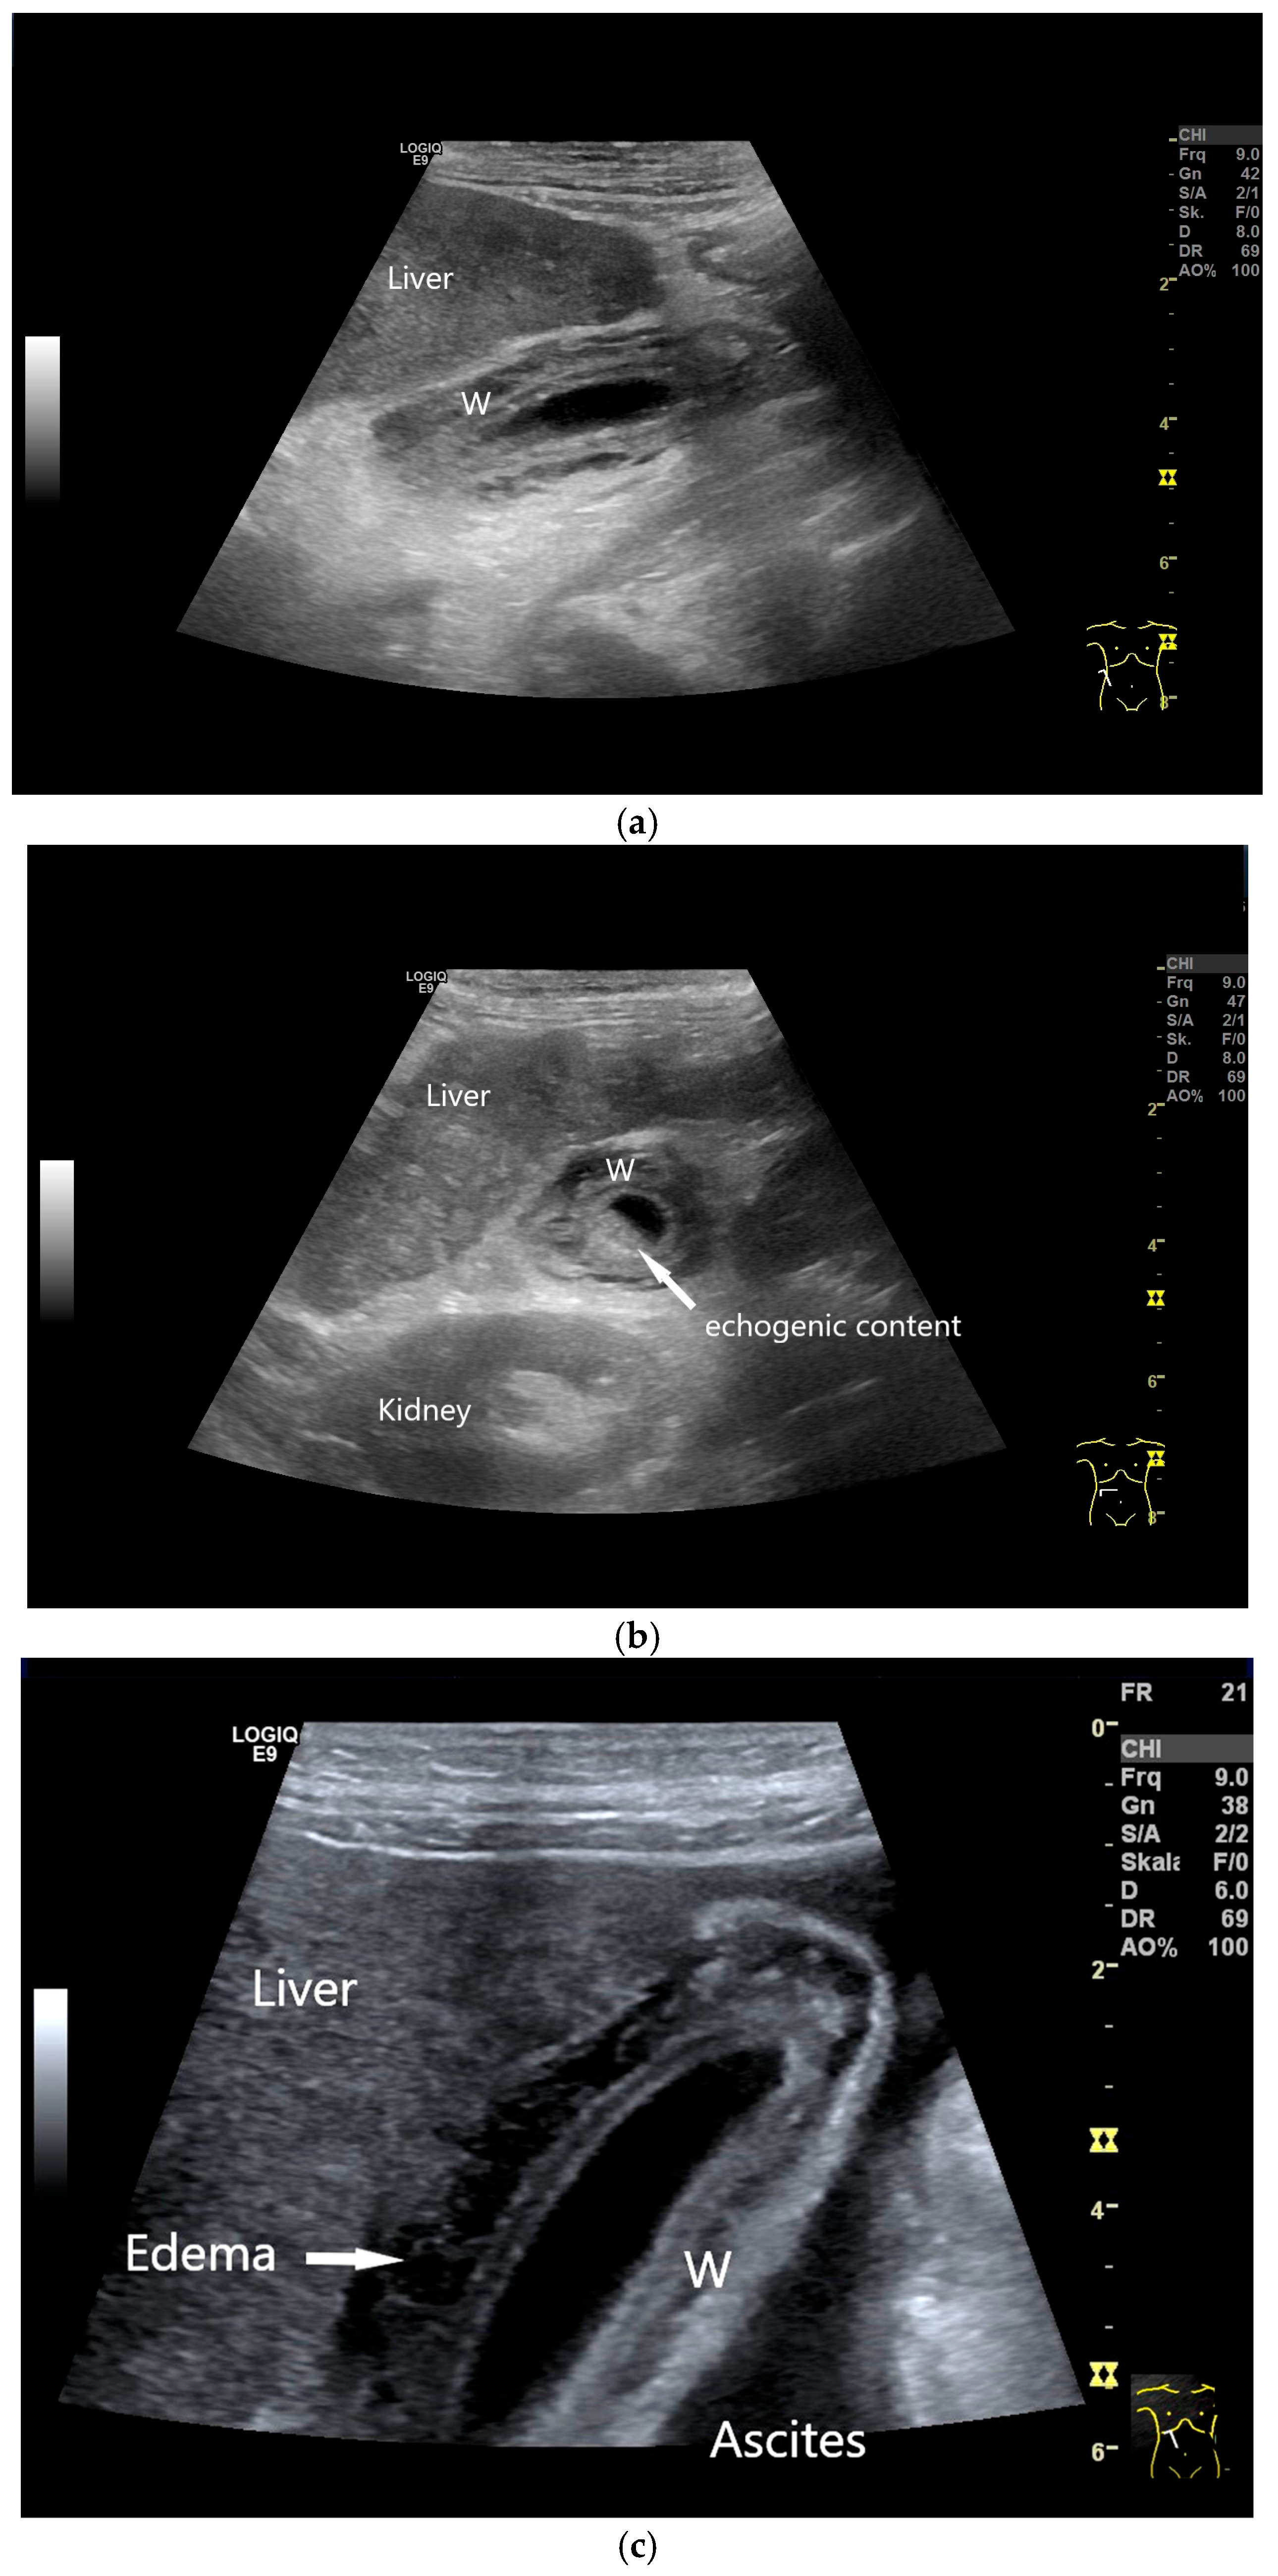

4.1. Diffuse Gallbladder Wall Thickening

- Vriesman, A.C.v.B.; Engelbrecht, M.R.; Smithuis, R.H.M.; Puylaert, J.B.C.M. Diffuse gallbladder wall thickening: Differential diagnosis. Am. J. Roentgenol. 2007, 188, 495–501. [Google Scholar] [CrossRef]

- Gupta, P.; Marodia, Y.; Bansal, A.; Kalra, N.; Kumar-M, P.; Sharma, V.; Dutta, U.; Sandhu, M.S. Imaging-based algorithmic approach to gallbladder wall thickening. World J. Gastroenterol. 2020, 26, 6163–6181. [Google Scholar] [CrossRef]